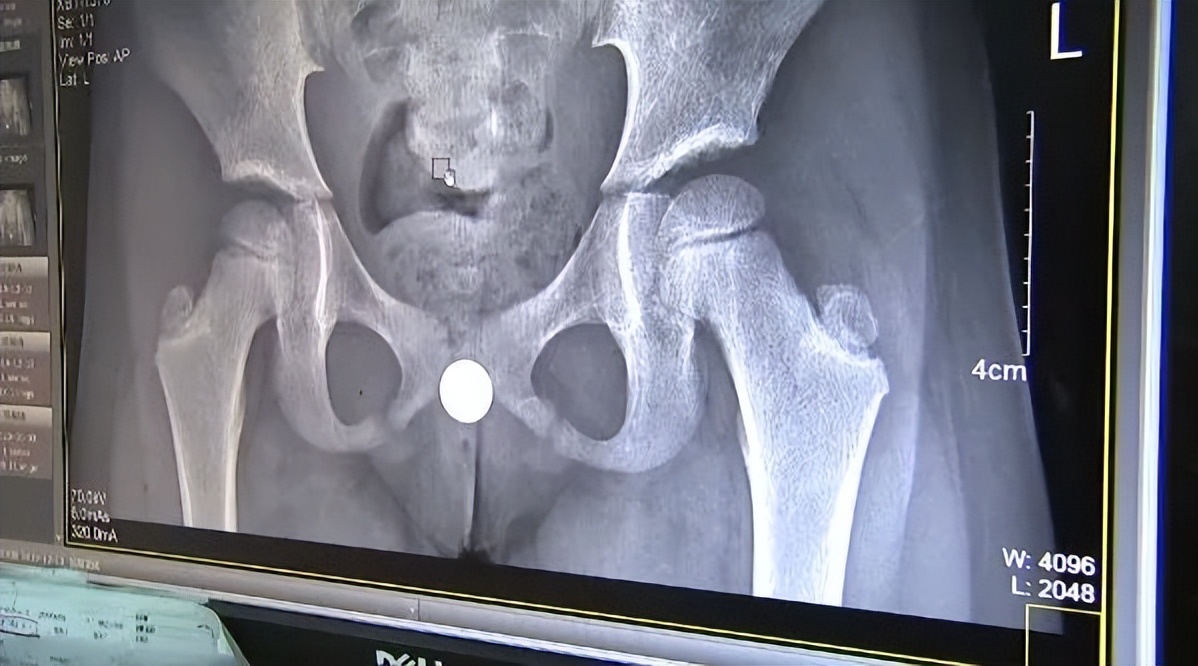

西安一名11岁男孩往膀胱里塞了19粒磁珠,过了一年才取出!

这些珠子连在一起长达10公分左右,又因为有磁性,医生最后通过手术切开小口才将珠子取出来。

医生介绍称,孩子是出于好奇在一年前将磁珠塞入*体下**的,期间虽然不适但一直没有求助父母。